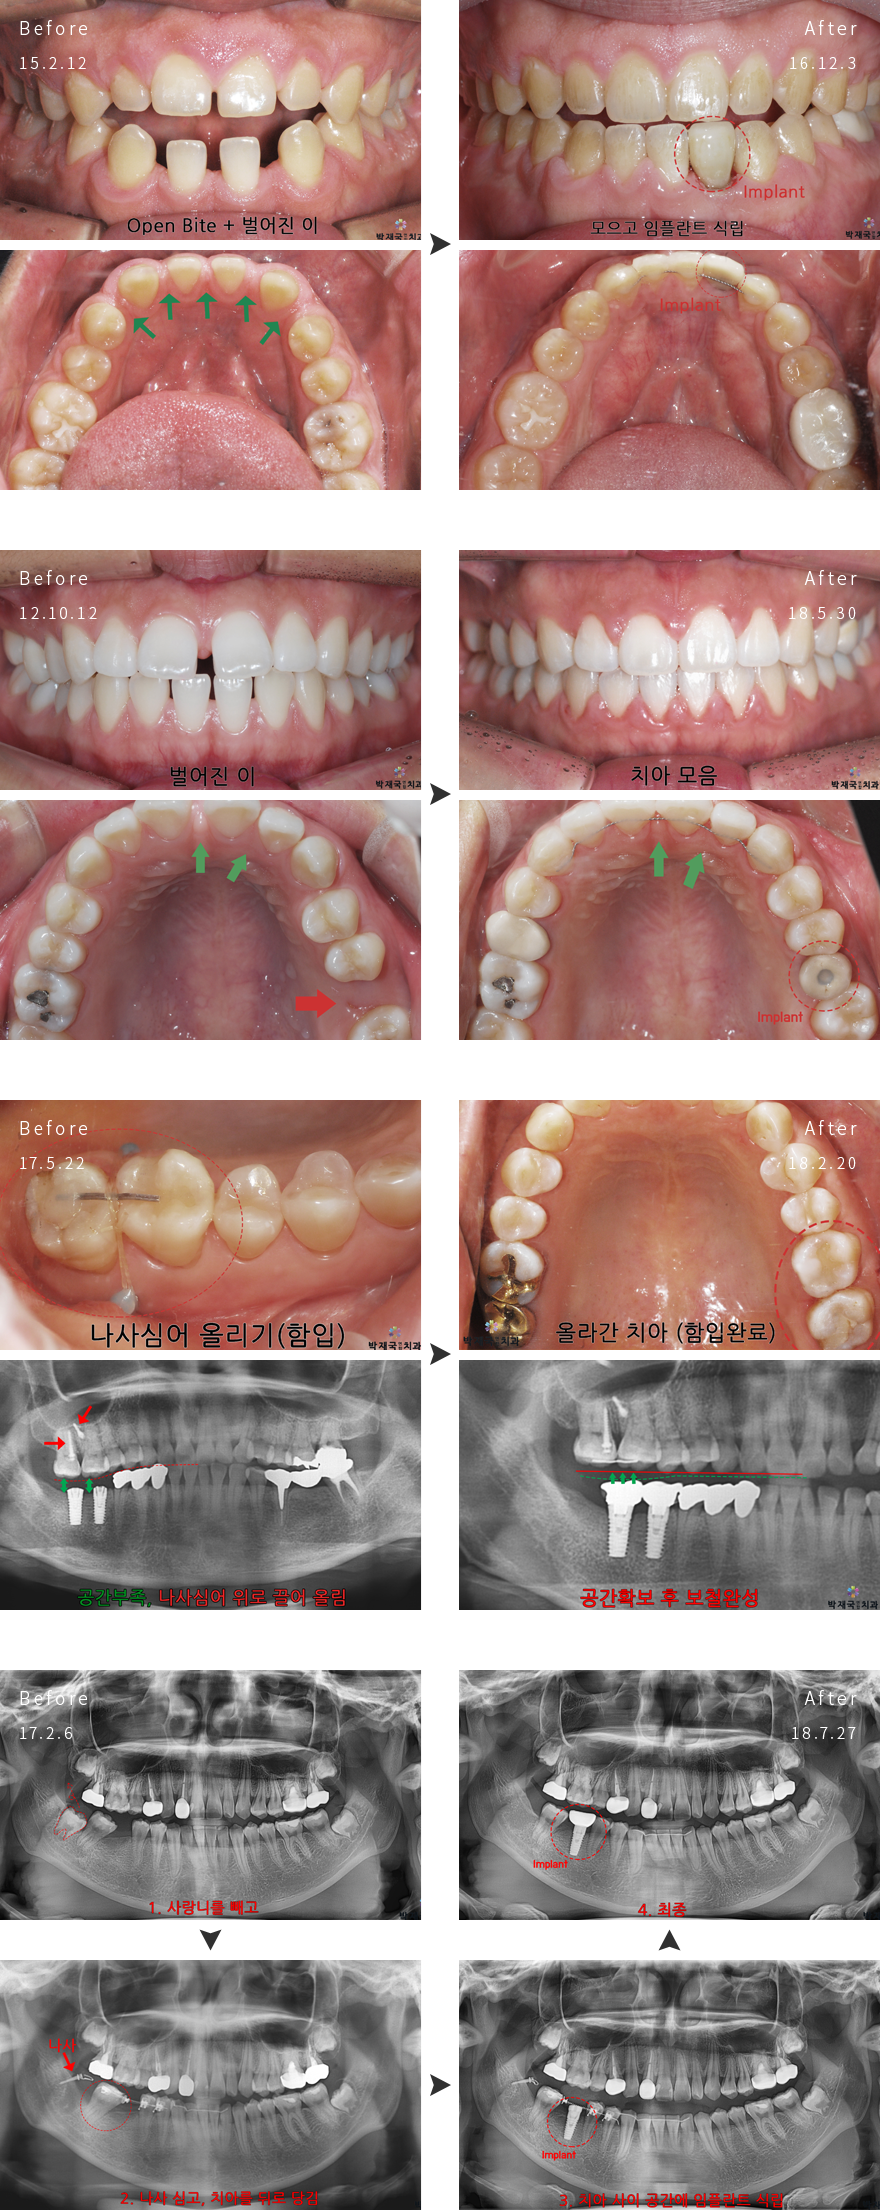

¼ºÀÎ/ºÎºÐ±³Á¤ »ç·Ê

orthodontic Clinic